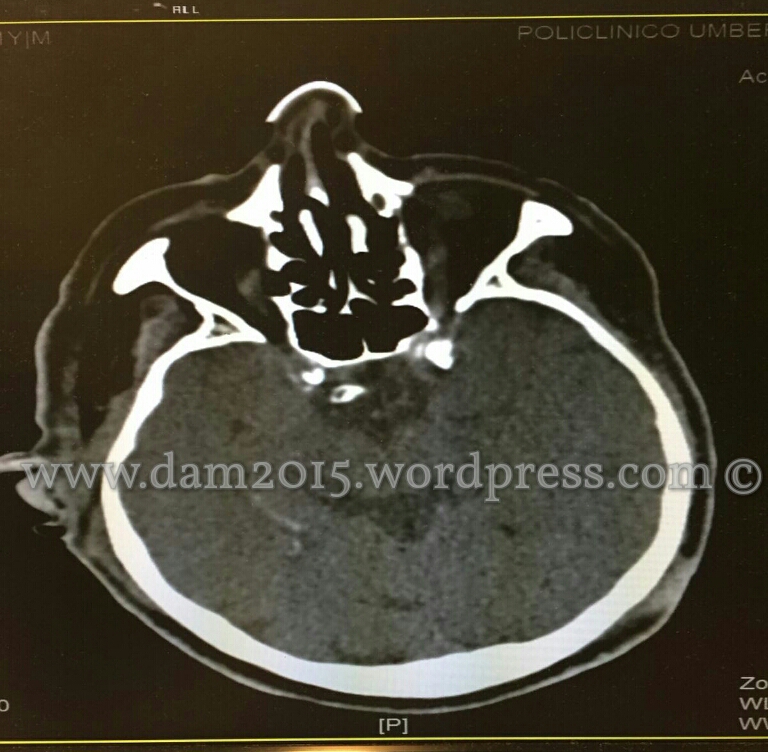

Si esegue TC total body:

-CRANIO, verniciatura iperdensa di verosimile significato ematico in sede temporale profonda destra. Presenza di bolle aeree in sede temporale e auricolare destra